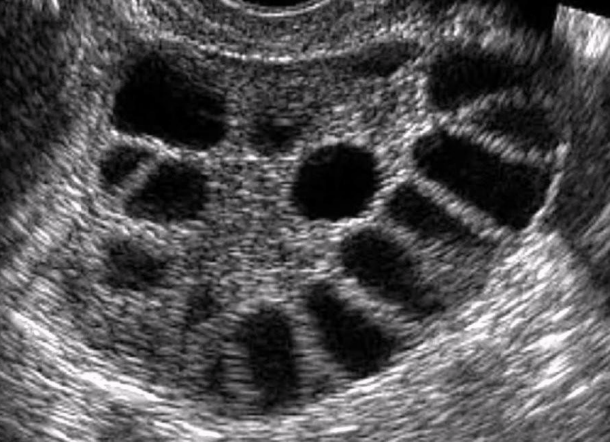

What sign is this?

a. Murphy’s sign

b. Tip of the iceberg sign

c. String of pearls sign

d. WES sign

Tip of the iceberg sign